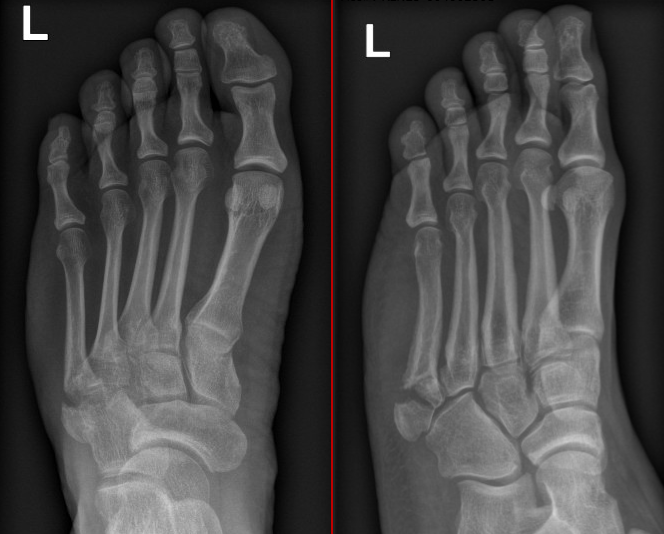

Case 2 - delayed presentation of inversion injury

Figure 4: Discplaced, intra-articular, communted fracture with signs of early sclerosis

Figure 5: 3 months following compression screw fixation with signs of early failure / non-union

Figure 6: 3 months following revision fixation and cancellous autograft (from heel)